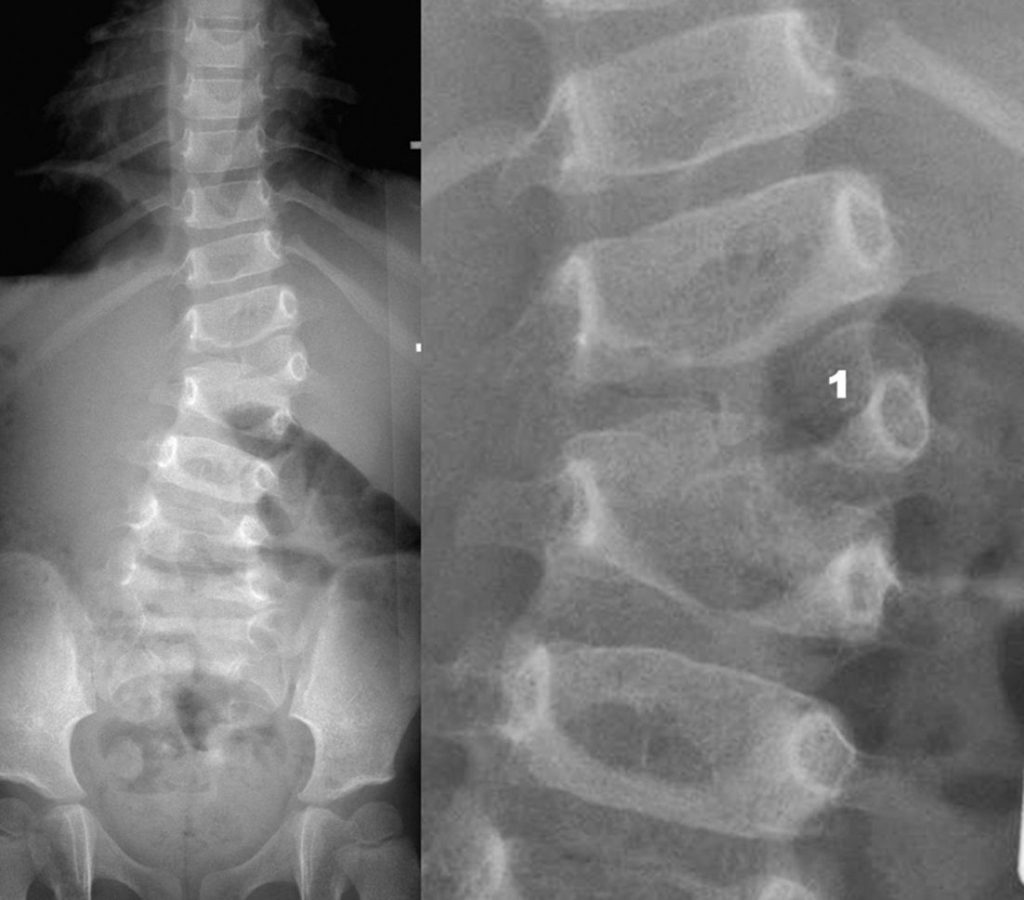

Fig. 119.3 Autre exemple : scoliose malformative.

Il existe une courbure rachidienne lombaire à convexité droite en rapport avec une hémivertèbre droite surnuméraire (1) entre L1 et L2.

Source : CERF, CNEBMN, 2022.